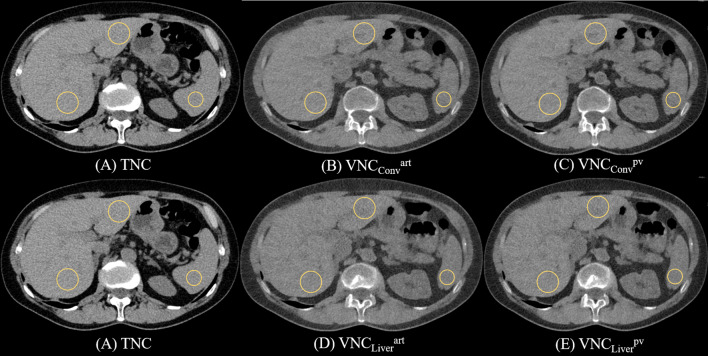

Photon counting detector CT-derived virtual non-contrast images of the liver: comparison of conventional and liver-specific algorithms across arterial and portal venous phase scans.